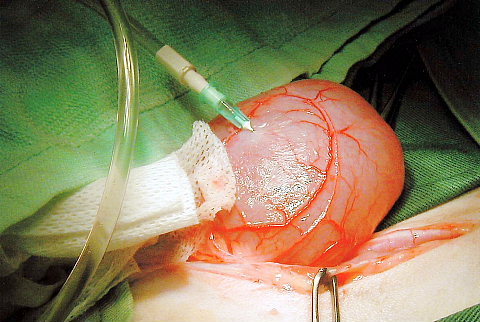

次も鼠径ヘルニアなんですが、ヘルニアの内容物がちょっと珍しいんですけど卵巣と子宮でした。

通常卵巣がここに落ち込むってことは考えられないんですが・・・

正直手術をしてびっくりでした。まさかこんなものがこんなところに、という感じでしたね。

この症例の発症原因ははっきりしなかったんですが、もう二度と見ることはないと思います。